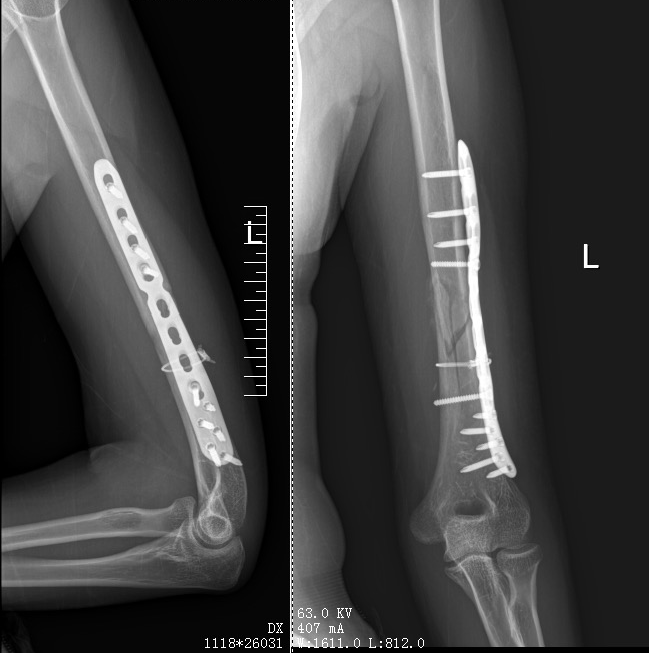

结合X光检查结果,张女士被诊断为左侧肱骨中下段骨折,左侧上臂桡神经损伤。好在后续治疗很顺利,目前张女士已经出院。

其实,掰手腕是一项比拼臂力和腕力的运动。除了需要手部、腕部肌肉的力量以外,前臂屈肌、肱二头肌、肱桡肌、肱三头肌等也均会被带动。肱骨下段承受很大的旋转应力,着力点正好在中下段位置。掰手腕时,对手通过前臂施加外旋应力,自身内旋肌群施加内旋应力,两者在肱骨最薄弱处(中段圆柱体向远端三角形过渡区域)形成巨大扭转应力,易导致螺旋形骨折。